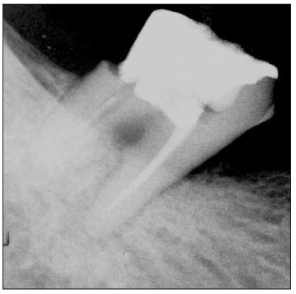

Figure 5

Diagnostic intraoral radiograph.

Figure 5 Diagnostic intraoral radiograph.